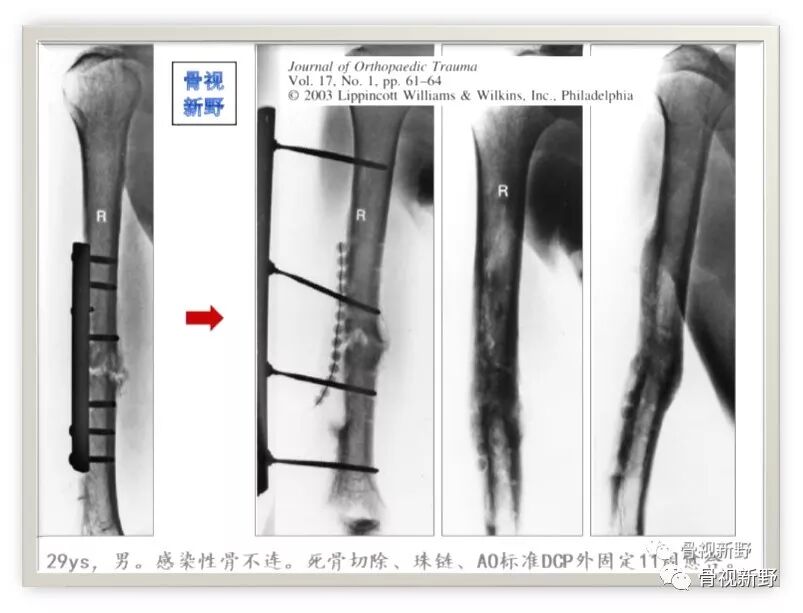

第三次报道:

2003年,Rene K.Marti团队再次报道了将AO标准钢板作为外固定架用于开放性骨折以及骨感染性骨不连的固定病例31例,也取得了较好的疗效。

锁定钢板的外固定应用

Cases